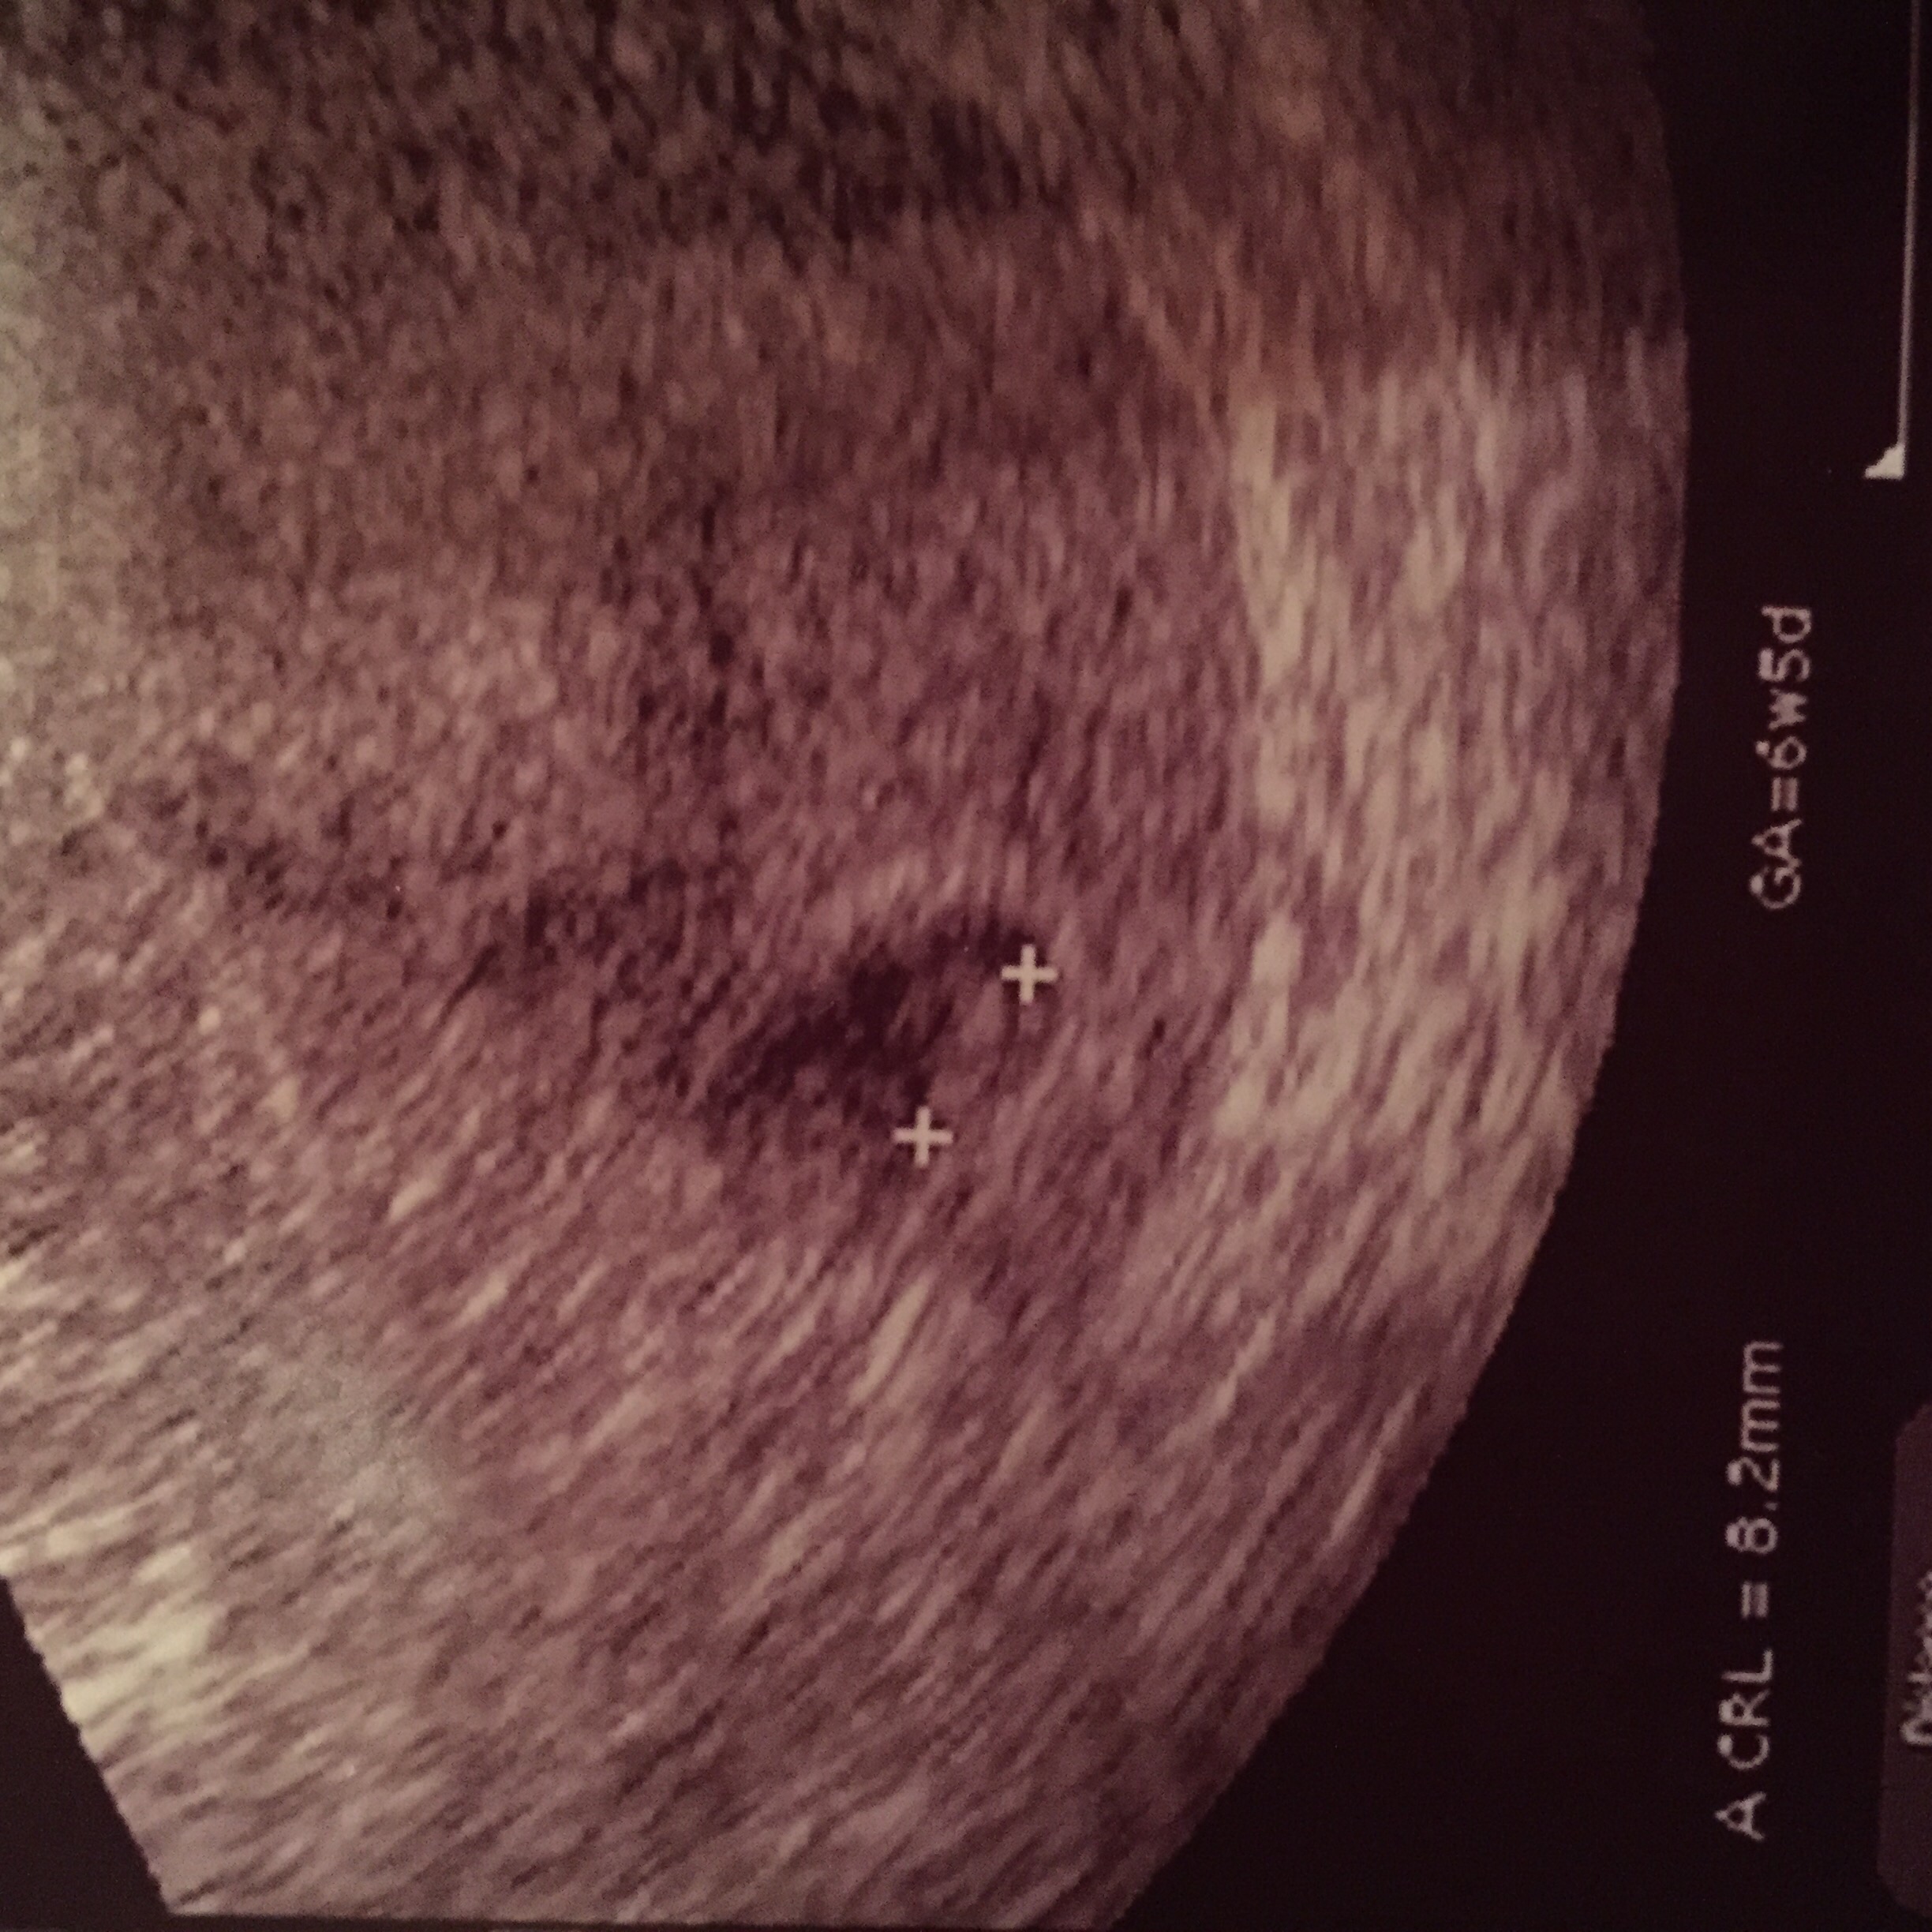

• Had our ultrasound Thursday. I'm measuring 6w1d. We saw the heartbeat. It was right at 151bpm. We go back again at 10 weeks. I can't wait!!!